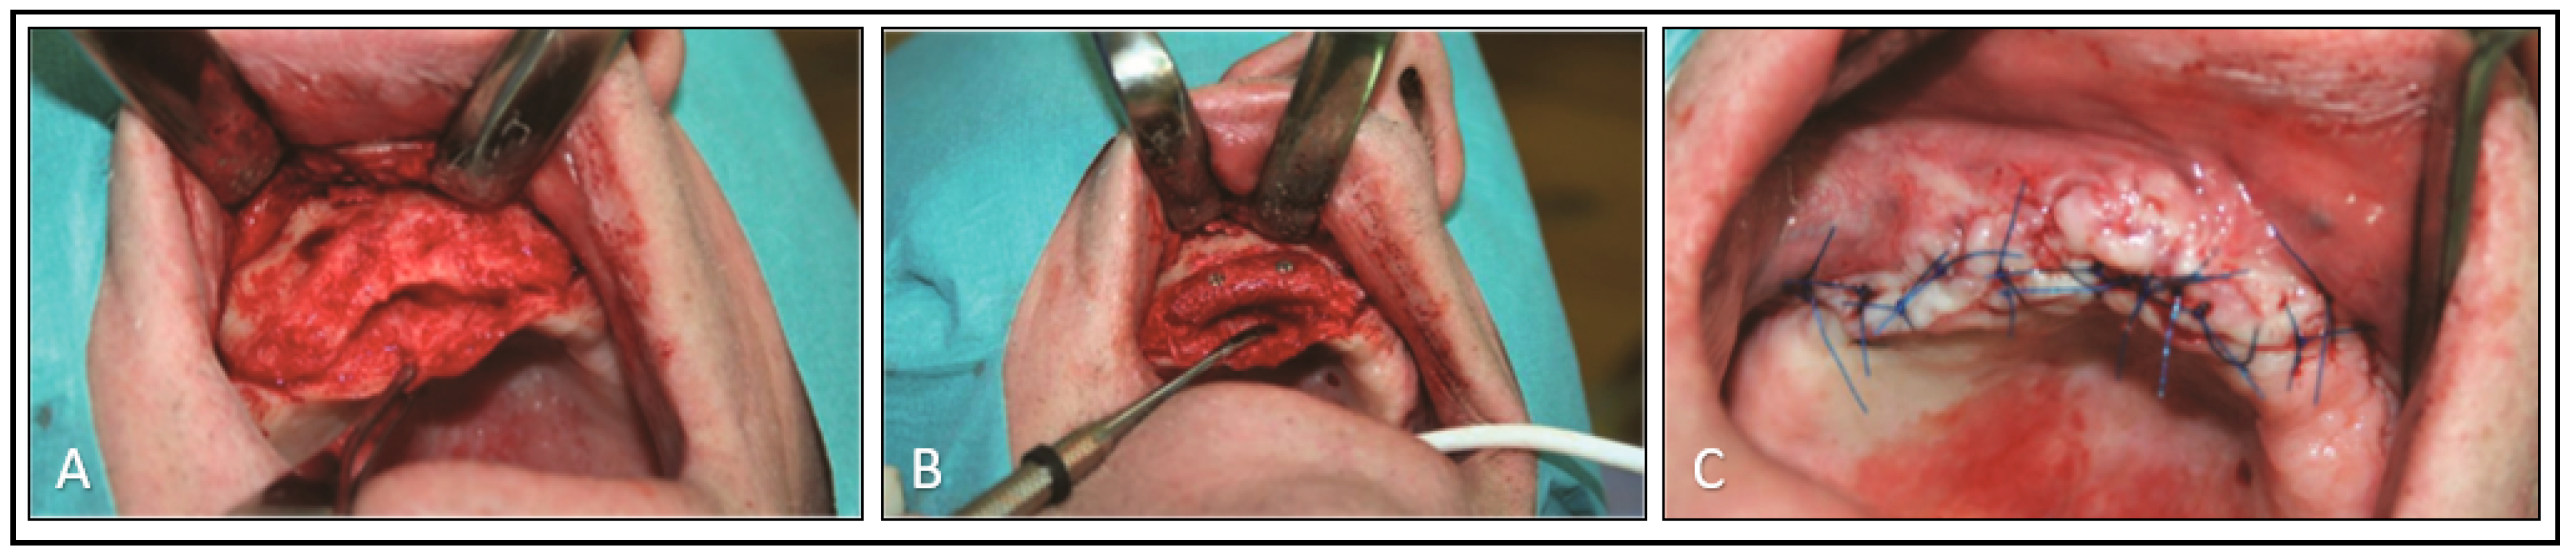

2. Case Report

2.2. Surgical Phase